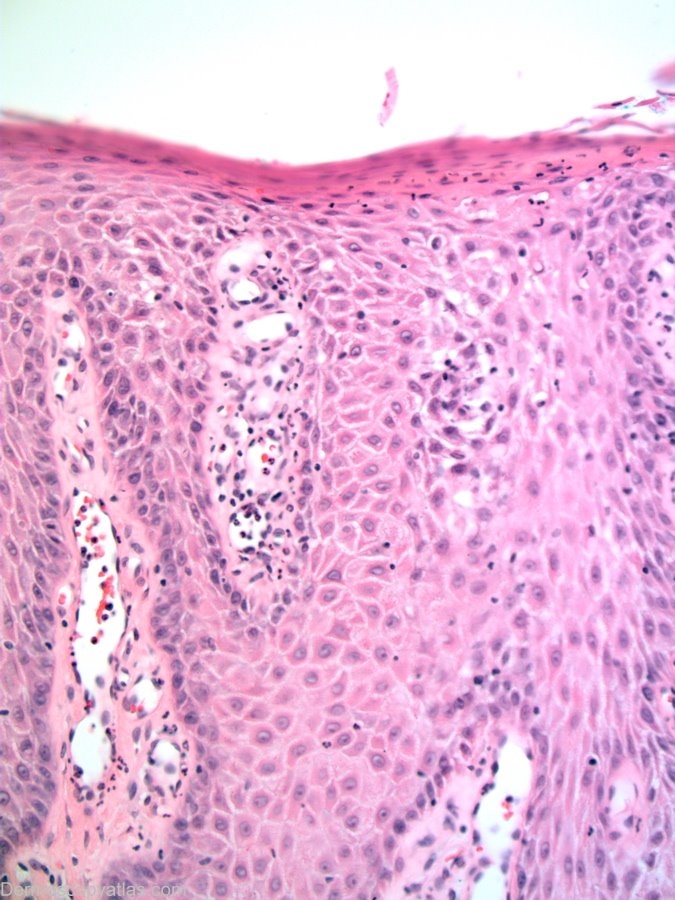

Diagnosis: Clear cell acanthoma

Description: Lesion on the chest wall. Note the string of pearls vessels and the glycogen rich keratinocytes giving the lesion its histological clear colour.